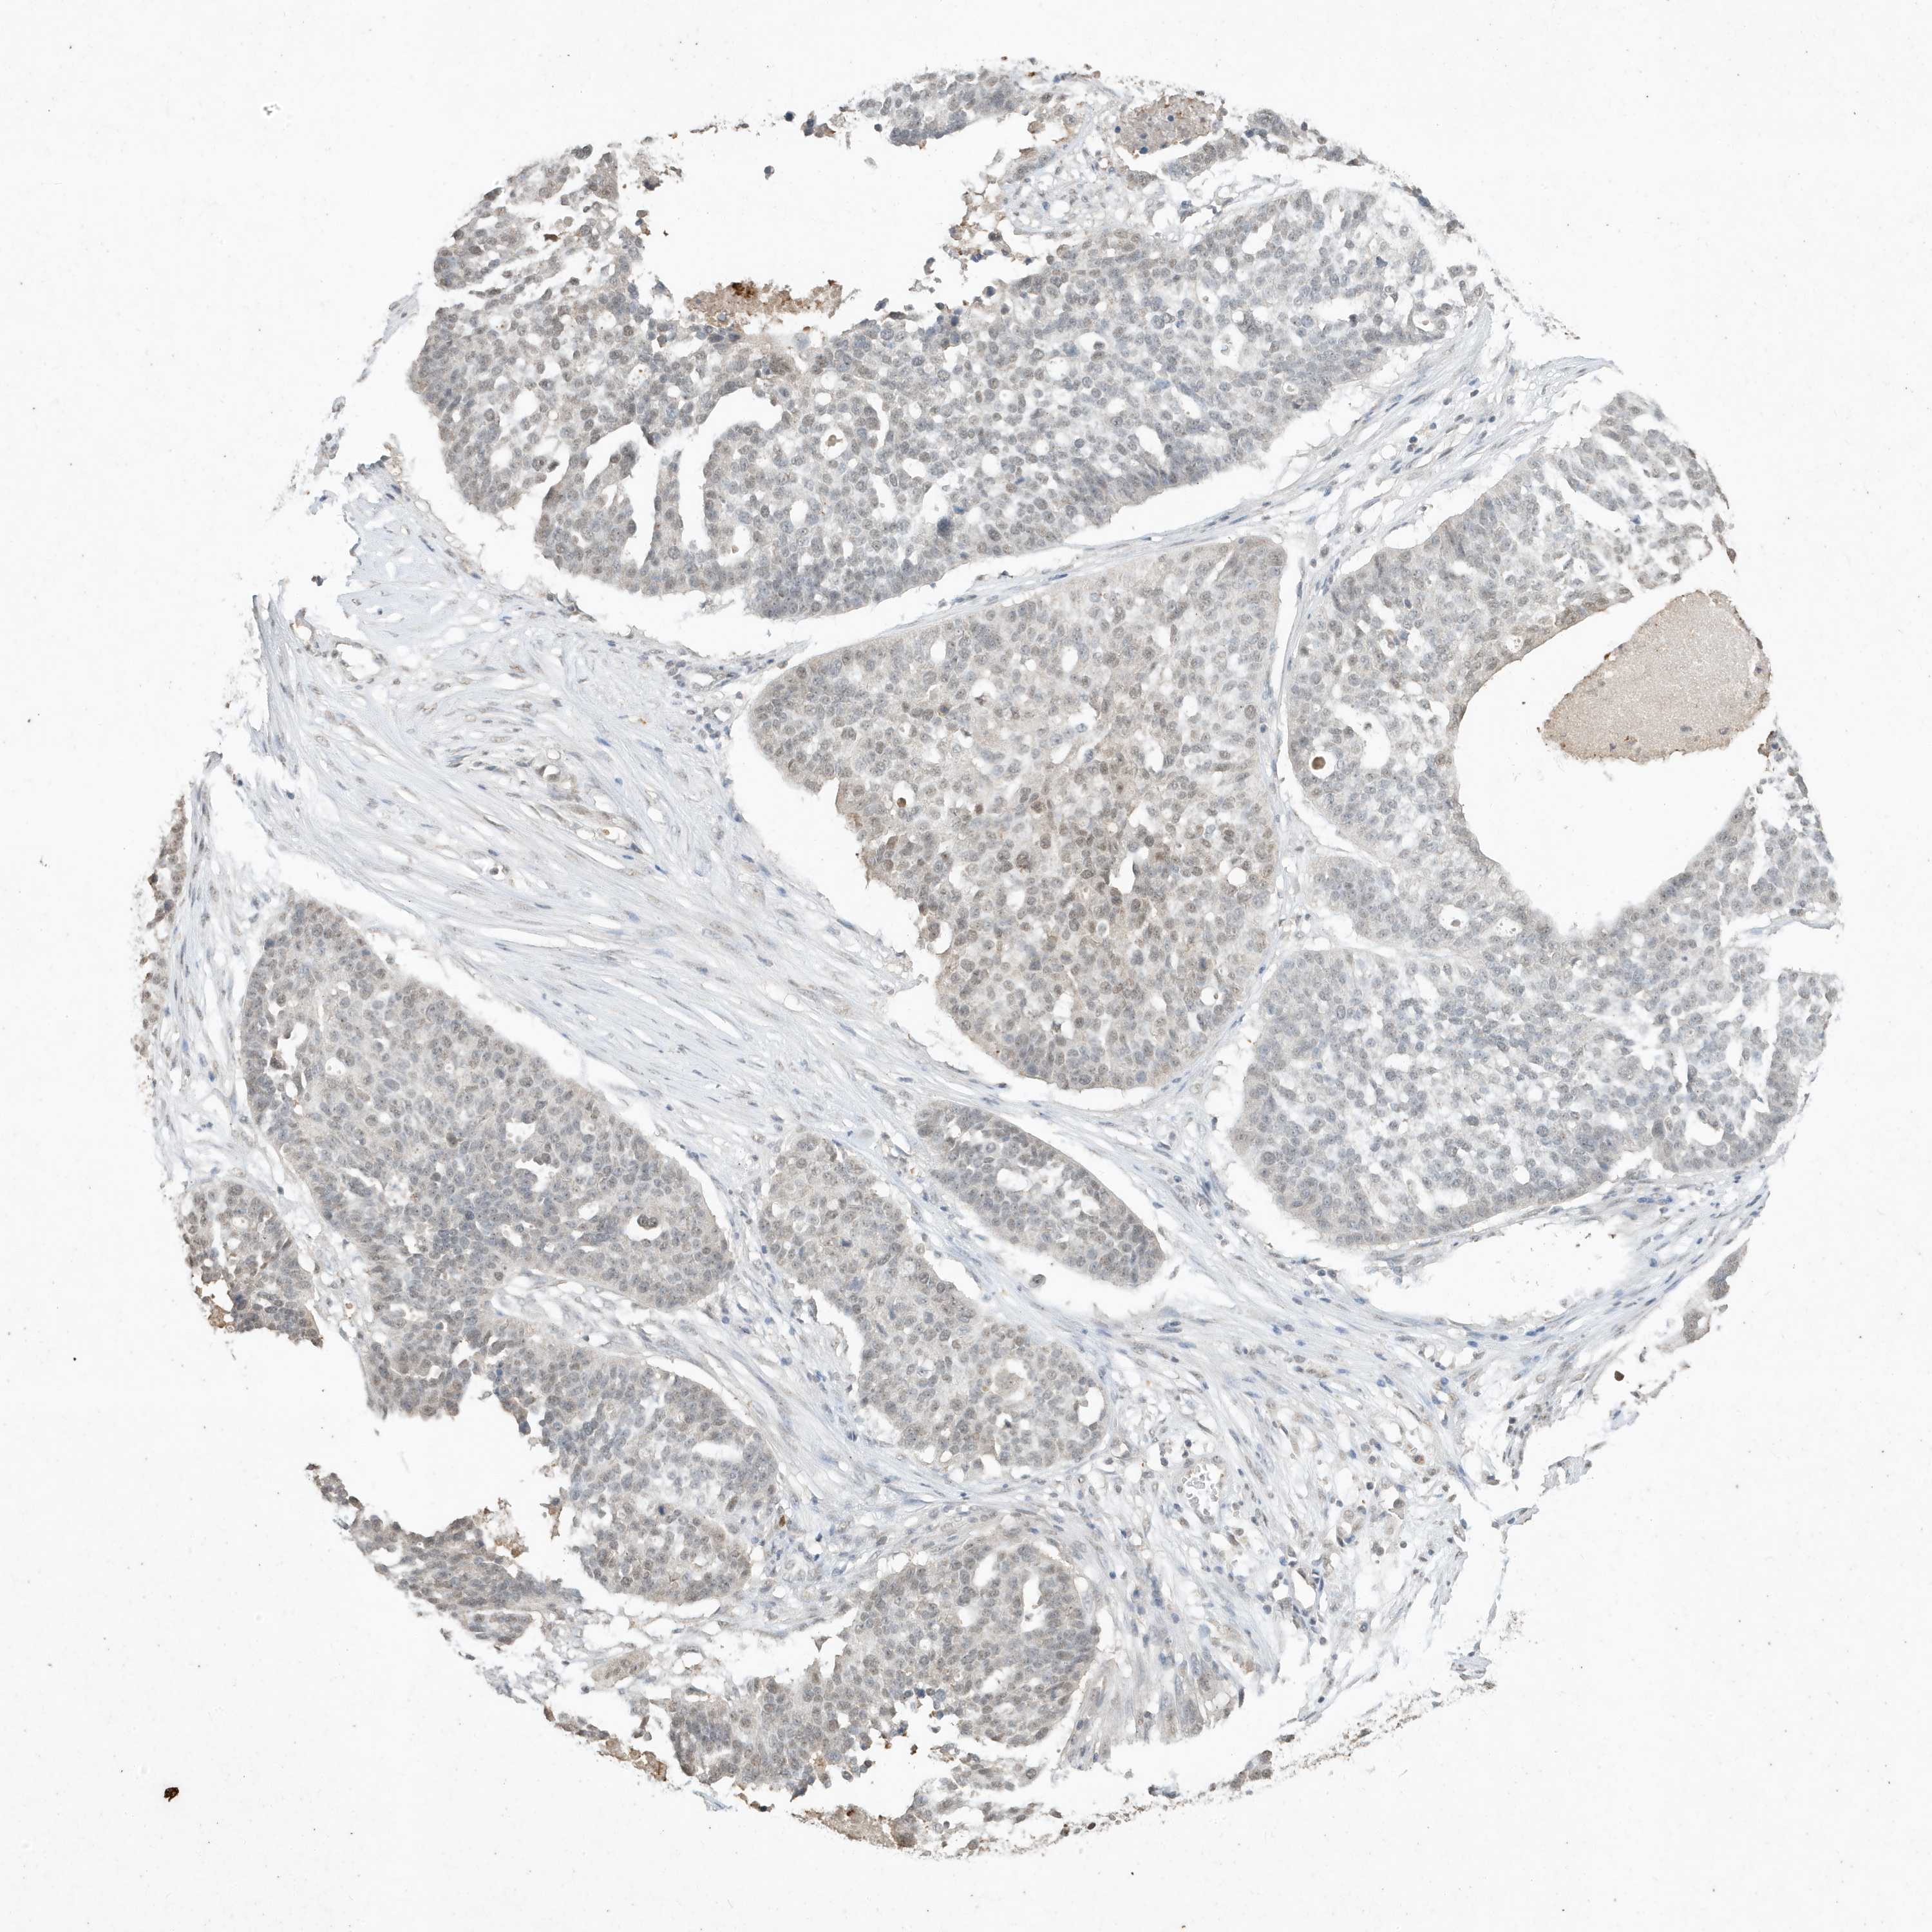

OVARIAN CANCER - Protein expressioni

A mouse-over function shows sample information and annotation data. Click on an image to view it in a full screen mode. Samples can be filtered based on level of antibody staining by selecting one or several of the following categories: high, medium, low and not detected. The assay and annotation is described here.

Note that samples used for immunohistochemistry by the Human Protein Atlas do not correspond to samples in the TCGA dataset.

Antibody stainingi

Antibody staining in the annotated cell types in the current human tissue is reported as not detected, low, medium, or high, based on conventional immunohistochemistry profiling in selected tissues. This score is based on the combination of the staining intensity and fraction of stained cells.

Each image is clickable and will lead to virtual microscopy that enables deeper exploration of all samples and also displays staining intensity scores, fraction scores and subcellular localization as well as patient and tissue information for each sample.

Antibody HPA052517

Antibody CAB032548

Staining

High

Medium

Low

Not detected

Intensity

Strong

Moderate

Weak

Negative

Quantity

>75%

75%-25%

<25%

None

Location

Nuclear

Cytoplasmic/membranous

Cytoplasmic/membranous,nuclear

Cystadenocarcinoma, serous, NOS

Cystadenocarcinoma, mucinous, NOS

Adenocarcinoma, NOS

Carcinoma, endometroid

Carcinoma, NOS